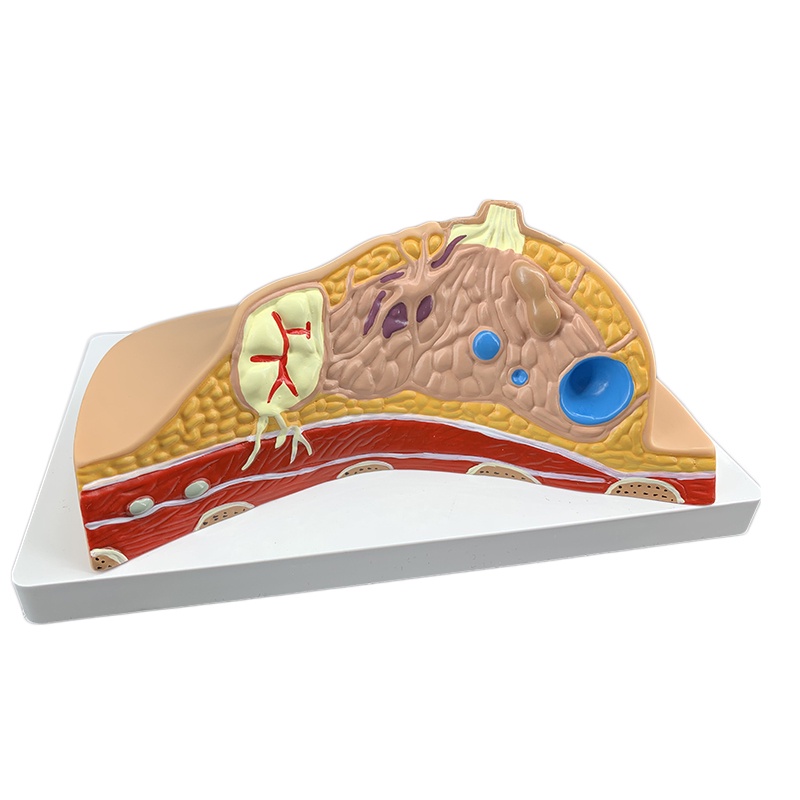

Median Section of Human Female Breast Cancer Anatomical Model Cyclomastopathy Breast Cancer Anatomy Model Medical Study